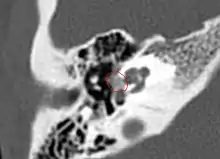

• CT scan of otosclerotic focus in the anterior footplate

Grade 3, diffuse confluent cochlear involvement (with or without fenestral involvement).